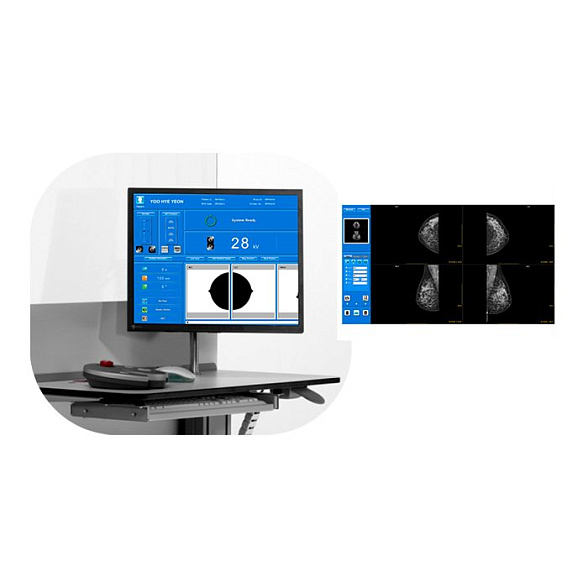

Bemems Pinkview АT Маммограф с комплексом компьютерной радиографии

Bemems Pinkview AT: Цифровой маммограф с комплексом компьютерной радиографии

Маммограф Bemems Pinkview AT представляет собой современную цифровую систему для ранней диагностики заболеваний молочной железы. Это комплексное решение, объединяющее в себе высокотехнологичный маммографический аппарат и рабочую станцию компьютерной радиографии (КР), что обеспечивает полный цикл получения и обработки диагностических изображений.

- Повышение производительности: Мгновенное получение изображения на монитор врача исключает время на проявку пленки, ускоряя процесс обследования и снижая вероятность технического брака.

Встроенная система компьютерной радиографии — это не просто сканер, а интеллектуальное звено, преобразующее информацию с imaging plate (CR-кассеты) в цифровой DICOM-файл. Комплекс включает в себя считывающее устройство, рабочую станцию со специализированным программным обеспечением для обработки и просмотра изображений, а также набор многоразовых CR-кассет. Это решение идеально подходит для модернизации существующих пленочных маммографов до цифрового уровня или для создания гибкой диагностической сети.

| Регулировка напряжения (кВ) | Автоматическая и ручная установка в диапазоне, оптимальном для маммографии (обычно 22-35 кВ) |

| Режимы съемки | Стандартные проекции: краниокаудальная (CC) и медиолатеральная косая (MLO). Возможность прицельной и увеличенной маммографии. |

| Программное обеспечение | Включает ПО для управления аппаратом, считывания CR-кассет, обработки, просмотра, архивации и передачи DICOM-изображений. |

Входит ли в комплект рабочая станция врача?

Да, комплекс компьютерной радиографии включает в себя рабочую станцию (компьютер, монитор медицинского класса, считывающее устройство и ПО), необходимую для обработки и анализа полученных изображений.